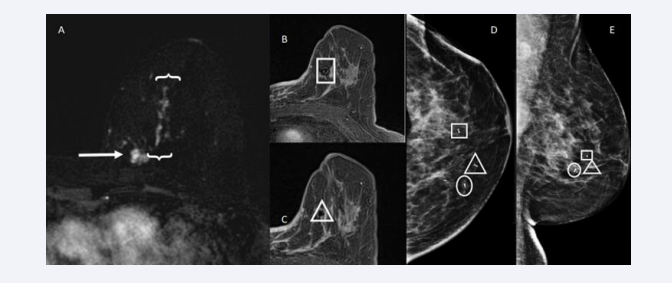

Clip marker placement was performed by one of 17 fellowship trained breast radiologists with one to over 30 years of experience along with trainees under their supervision. Preprocedural sagittal breast MRI images were obtained prior to and after the administration of gadolinium contrast (gadobenate dimeglumine [MultiHance, Bracco] or gadobutrol [Gadovist, Bayer HealthCare)]. The same type of contrast agent and the same dose of the contrast agent was utilized at both the diagnostic MRI and the procedural MRI whenever possible. Utilizing a manual technique and calculation based on localization of the targeted lesion relative to the fiducial marker placed in the fenestrated grid, the targeted lesion was localized. Utilizing sterile technique, local anesthetic was administered, and a small skin incision was made to advance the obturator into the lesion. Axial images were then obtained to confirm positioning of the obturator within the targeted lesion prior to marker placement. Once the appropriate position was confirmed, the clip marker was deployed. (Figure 1A)

A: T1-weighted post-contrast subtraction MRI shows a lobular mass with irregular margins in the left breast upper inner quadrant (arrow). This finding is  consistent with the index carcinoma. There is associated malignant appearing segmental, reticular non mass enhancement contiguous with the index mass extending  anteriorly and laterally (brackets). B and C: Post-contrast MRI show clip marker placement in the anterior-superior (square) and lateral (triangle) most extent of  enhancement. D and E: Craniocaudal and lateral post-clip mammography shows the index tumour (circle) and two ribbon clip markers delineating the anterior (triangle  and square) and lateral (square) most extent of disease. Final pathology showed invasive and in situ ductal carcinoma with negative margins.

Figure 1: A: T1-weighted post-contrast subtraction MRI shows a lobular mass with irregular margins in the left breast upper inner quadrant (arrow). This finding is consistent with the index carcinoma. There is associated malignant appearing segmental, reticular non mass enhancement contiguous with the index mass extending anteriorly and laterally (brackets). B and C: Post-contrast MRI show clip marker placement in the anterior-superior (square) and lateral (triangle) most extent of enhancement. D and E: Craniocaudal and lateral post-clip mammography shows the index tumour (circle) and two ribbon clip markers delineating the anterior (triangle and square) and lateral (square) most extent of disease. Final pathology showed invasive and in situ ductal carcinoma with negative margins.

A T1-weighted post-contrast image was obtained in the majority of cases at the radiologist’s discretion for assessment of clip deployment and post-procedural hematomas (Figure 1B,1C). The patient was then escorted to the mammography suite where craniocaudal and lateral medial or mediolateral mammograms were obtained. These images were evaluated to confirm successful clip marker deployment and to document potential clip migration (Figure 1D,1E). All patients subsequently underwent surgical excision with total mastectomy or breast conservation with mammographic localization utilizing wire, magnetic seed or radioactive seed guidance.